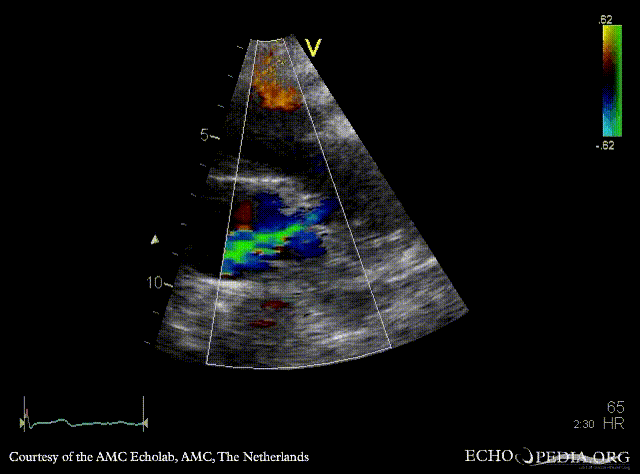

E00645.gif E00646.gif

Suprasternal view Suprasternal view with Color Doppler, open ductus Botalli